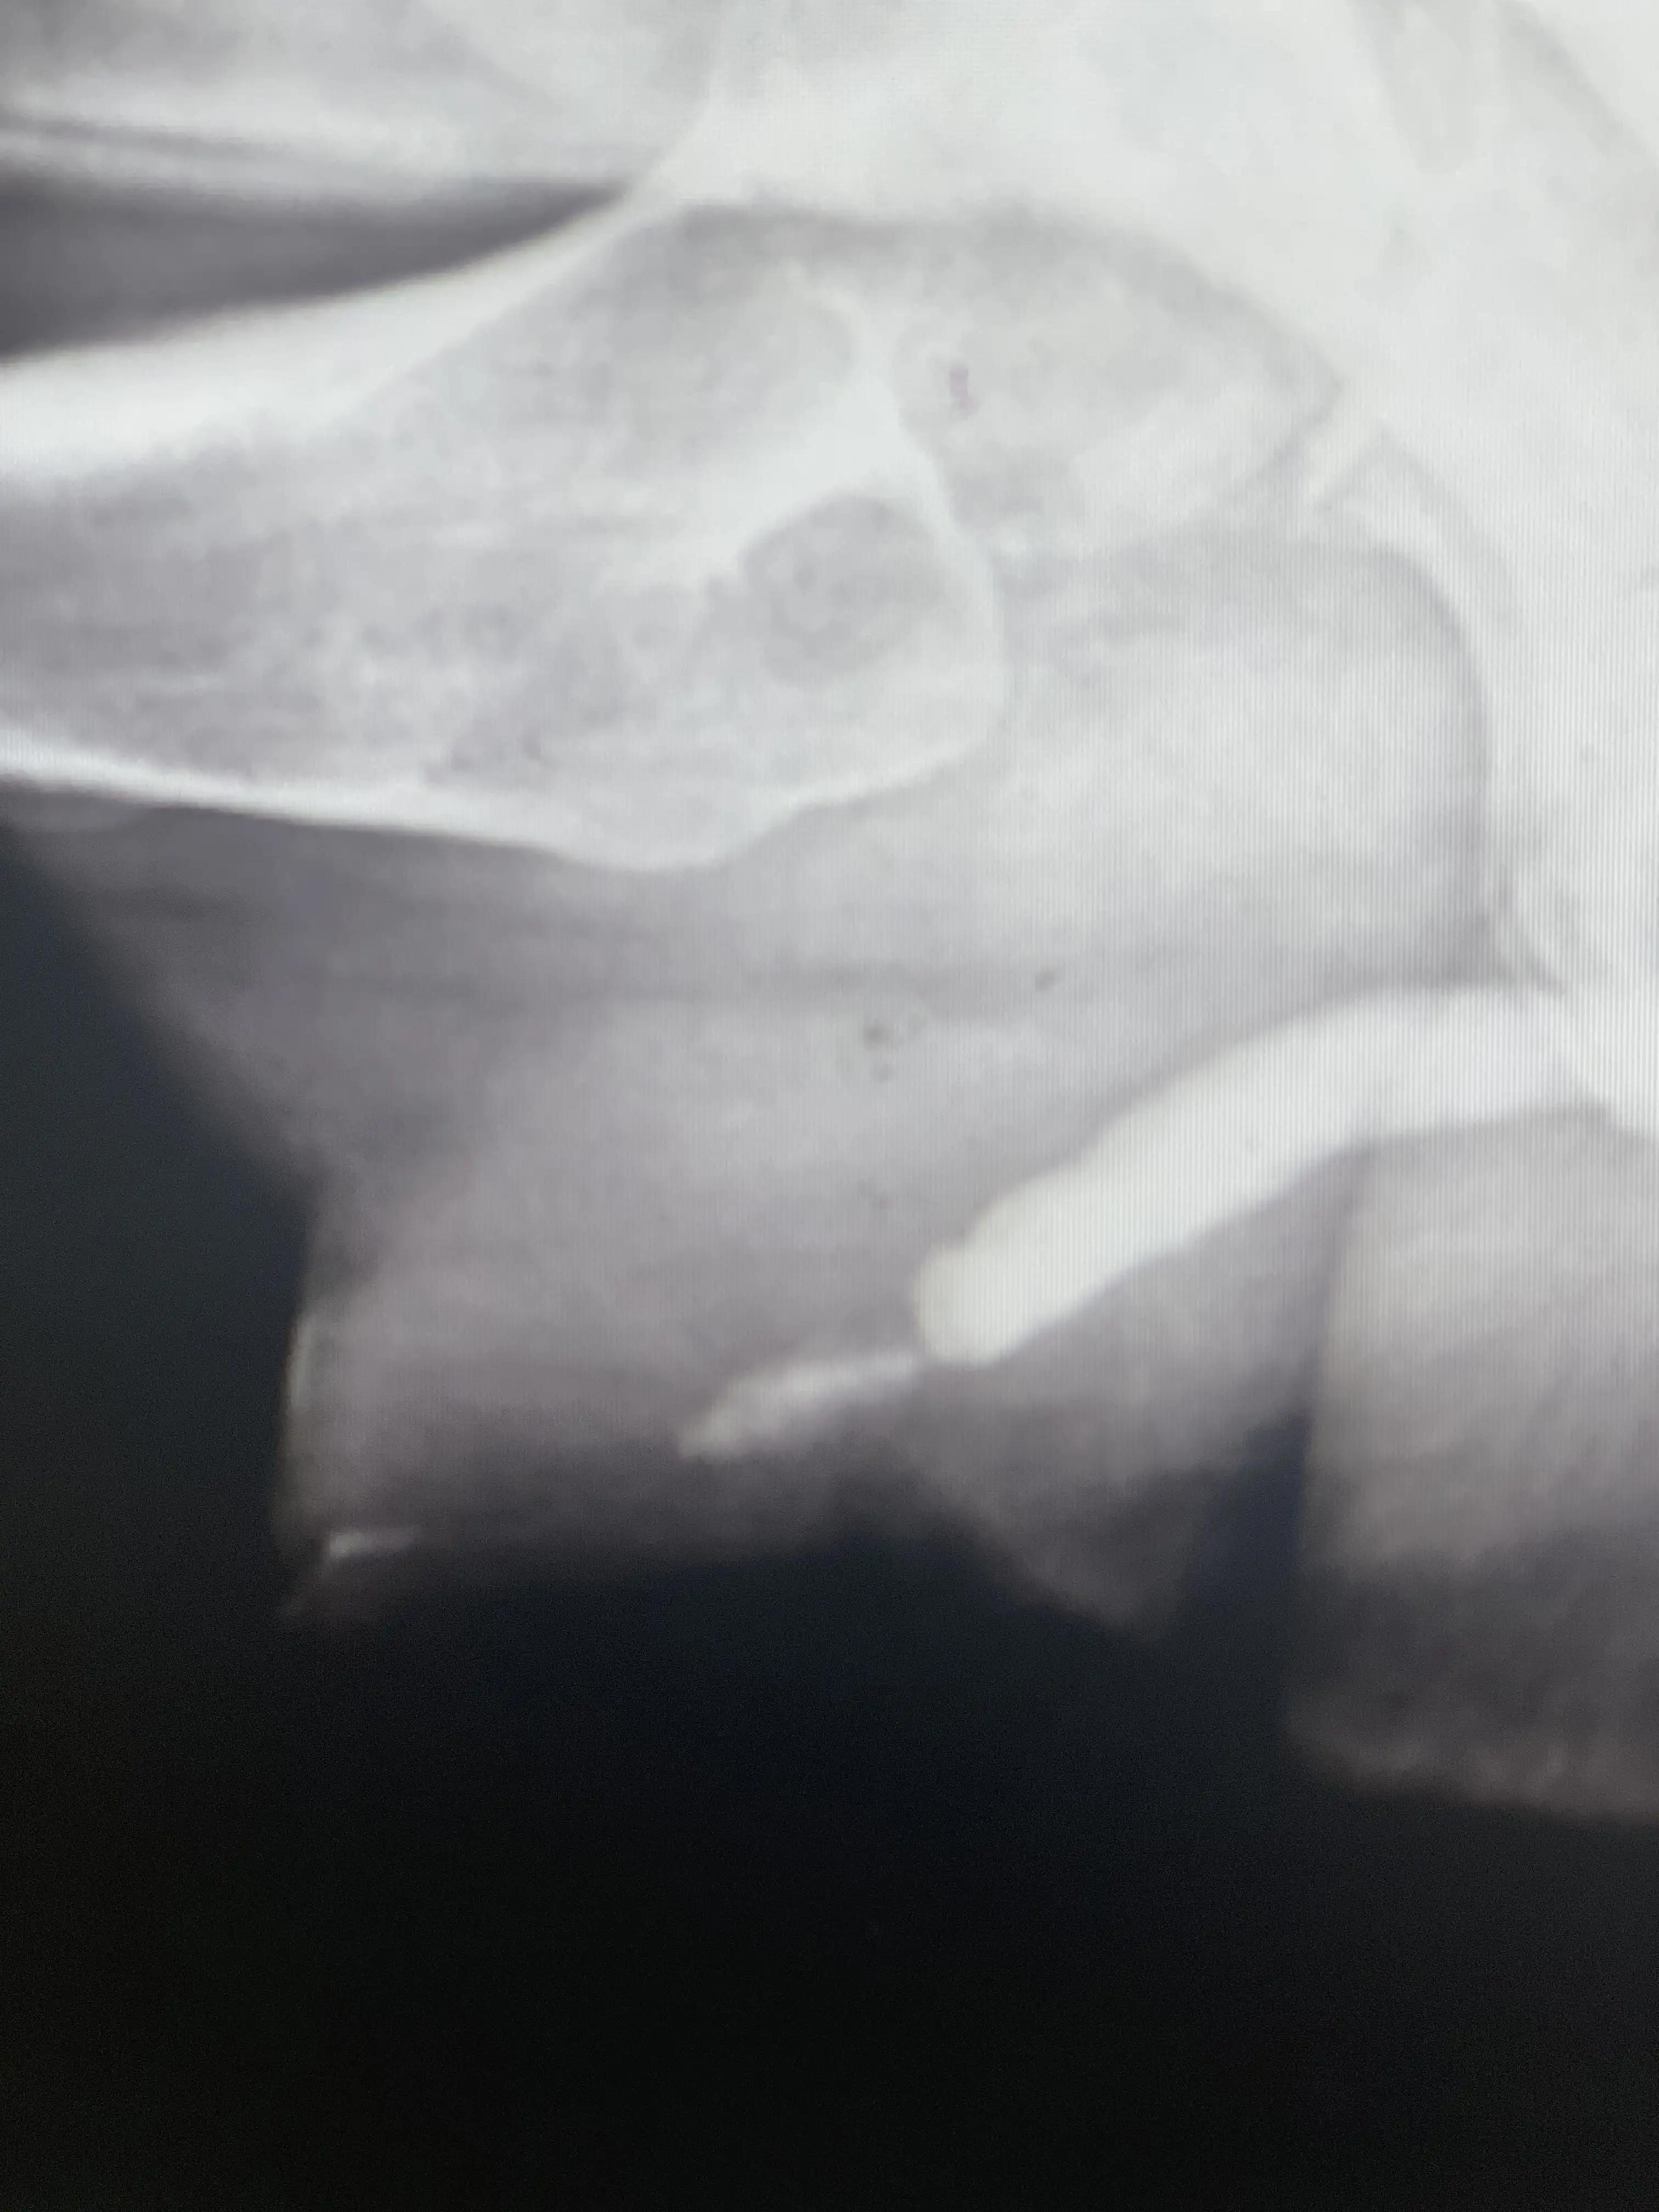

图四 排泄性膀胱尿道造影,尿道外口闭锁,长段前尿道狭窄

图五 排泄性膀胱尿道造影,尿道外口闭锁,膀胱容量正常